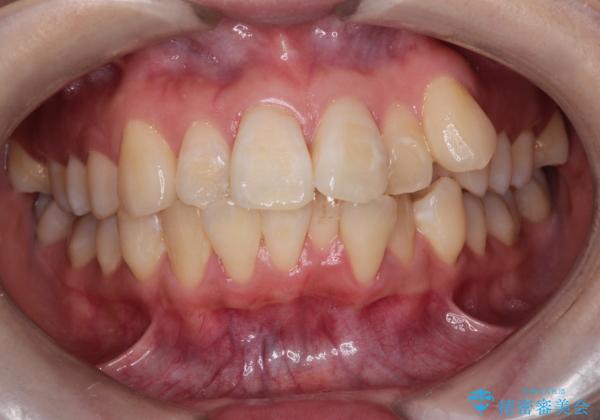

- 八重歯(叢生)と、上下の歯の中心線(正中)がずれていることを主訴にご来院されました。精密な検査の結果、歯列全体のスペースが大幅に不足しており、八重歯を正しい位置に配列し、正中のズレを改善するためには、上下左右の第一小臼歯を抜歯する必要があると診断。装置には、目立ちにくい審美ワイヤーを使用し、見た目を気にせず、機能性と審美性が完璧に整った咬み合わせを目指す治療計画を立案しました。

今回の矯正治療では、まず計画通り上下左右の小臼歯4本を抜歯し、八重歯や正中のズレを解消するための十分なスペースを確保しました。装置には、目立ちにくい白いブラケットとワイヤーを使用した審美ワイヤー矯正を採用。

八重歯: 突出していた八重歯を歯列内に誘導し、デコボコを解消しました。

正中のズレ: 歯を左右対称に移動させることで、上下の歯の中心線を正確に合わせ、顔全体のバランスも改善しました。

治療の結果、長年気にされていた八重歯と正中のズレが解消し、機能的にも整った理想的な歯並びを獲得。目立たない装置で治療を完遂し、自信を持って笑える美しい笑顔を手に入れていただけました。